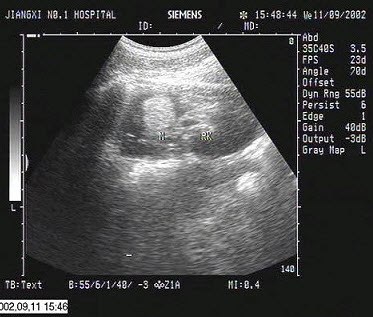

13、单项选择题

该病例最有可能诊断()

A.左房黏液瘤

B.主动脉瓣关闭不全

C.二尖瓣狭窄

D.二尖瓣关闭不全

E.二尖瓣脱垂

14、单项选择题